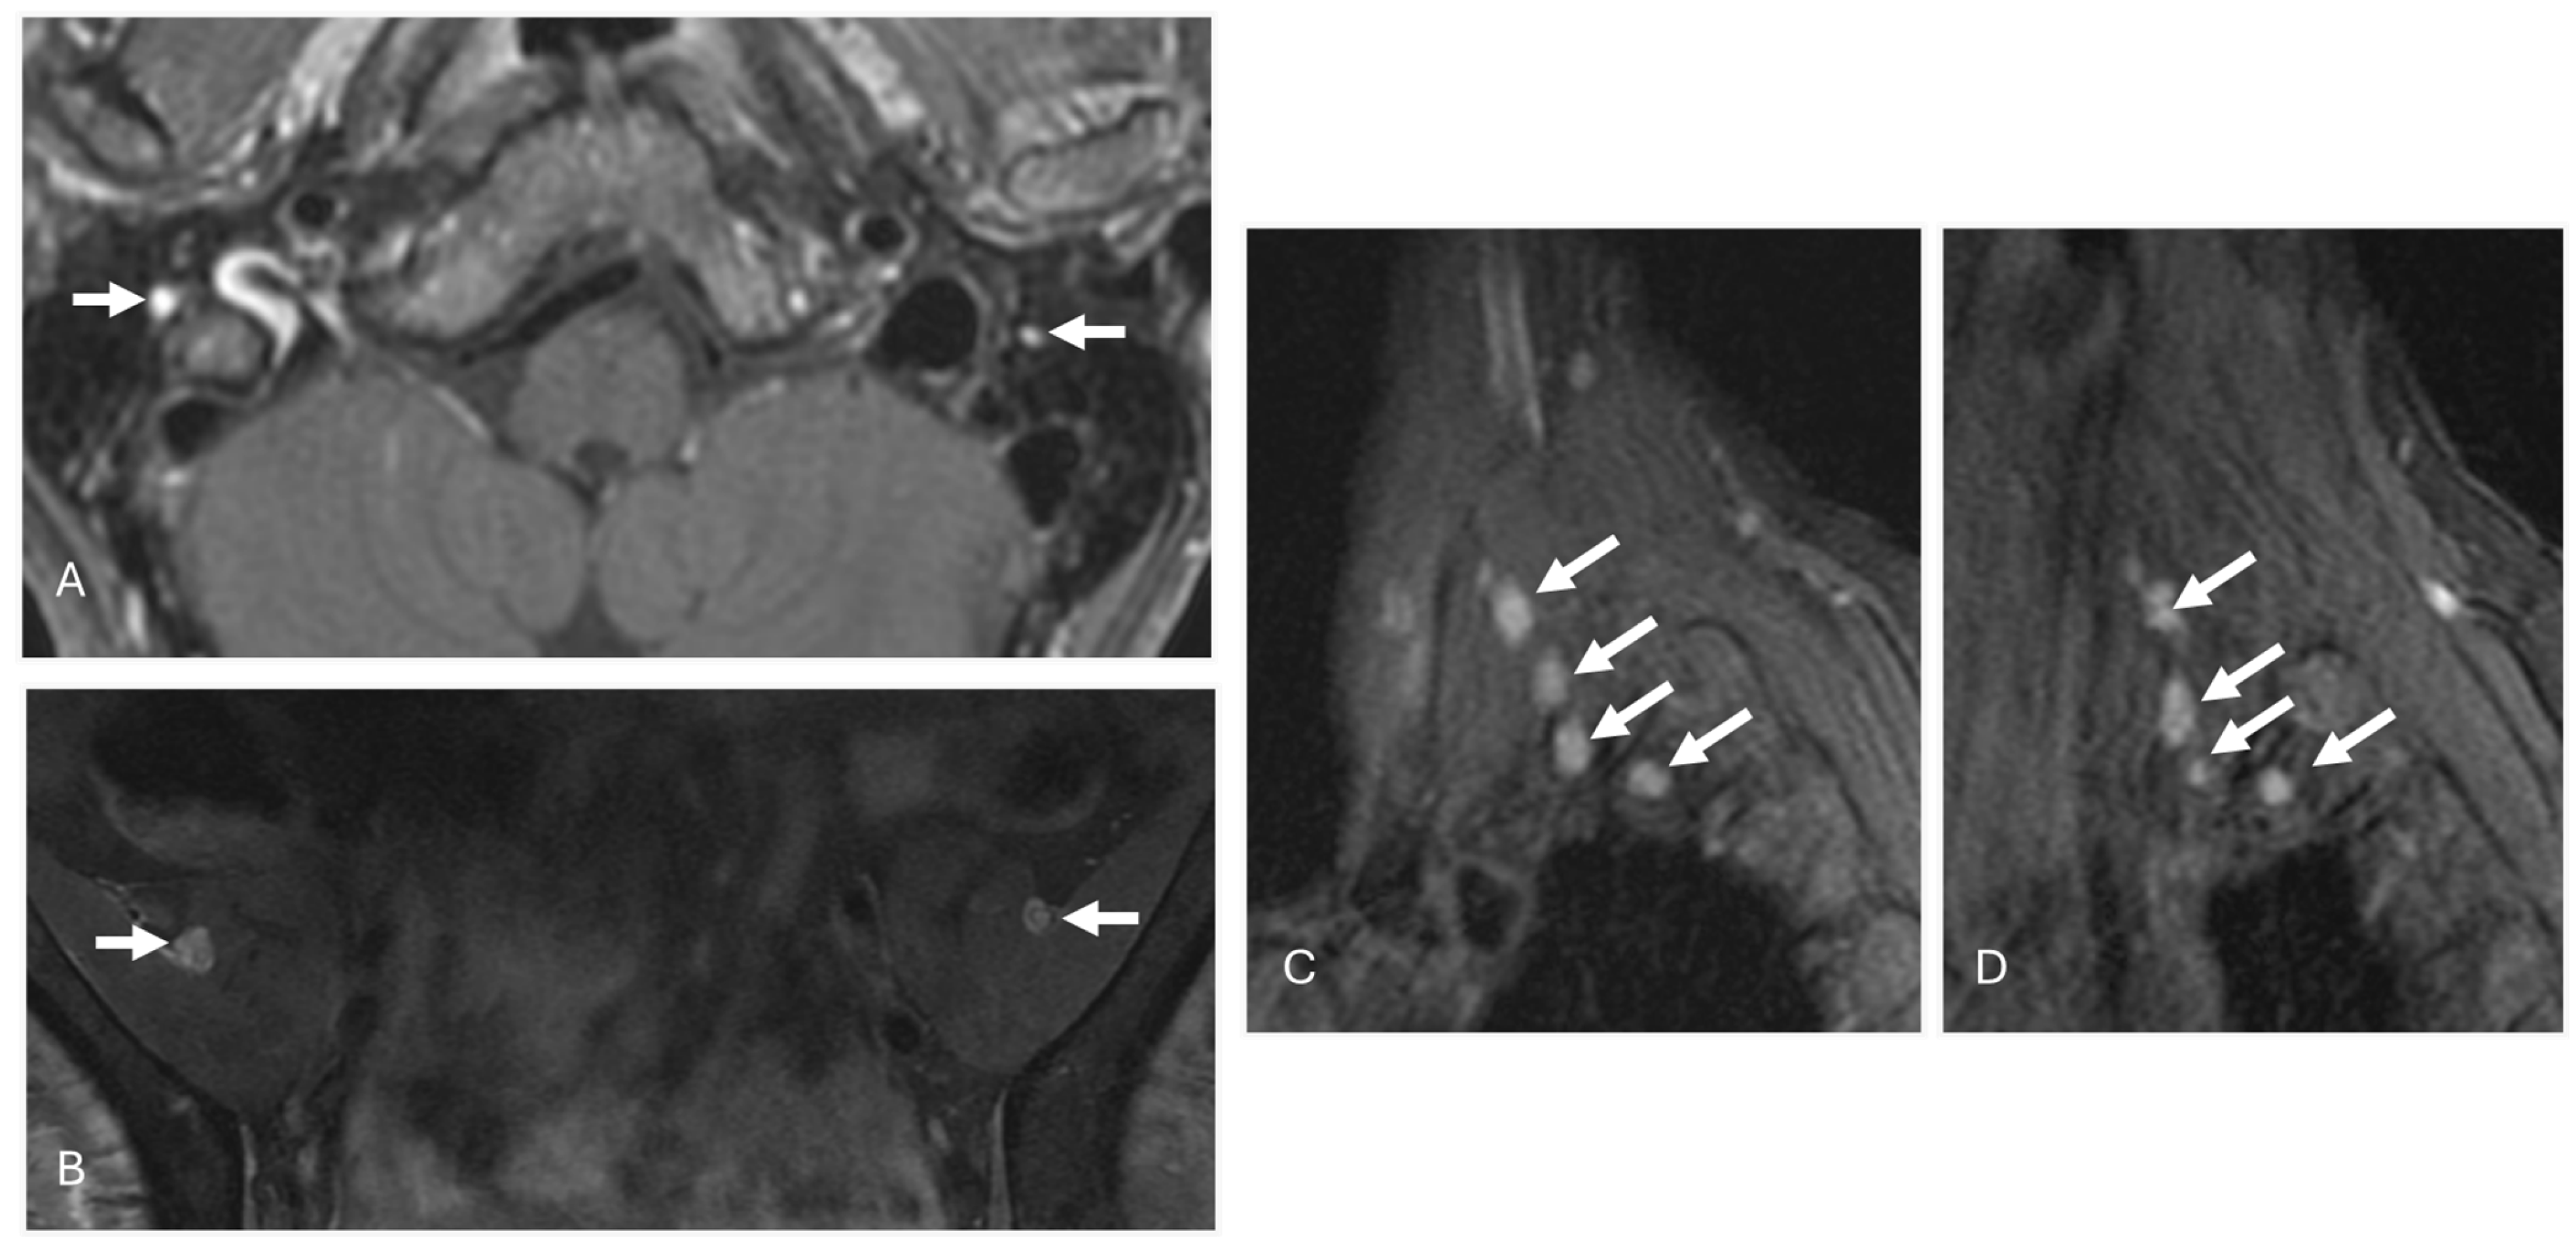

3.2. AL Amyloidosis

6. Imaging Considerations